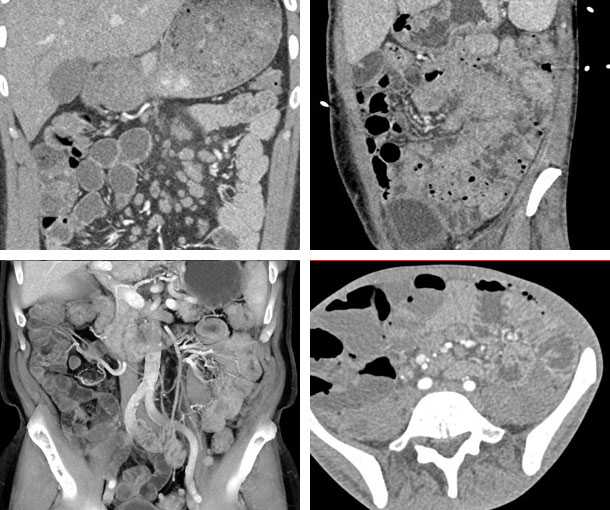

Mycobacterium Avium-Intracellulare (MAI) CT Findings

- Thickened small bowel folds

- Irregular diffusion

- Mesenteric adenopathy

- Low-attenuating nodes that are necrotic

- Enlargement of the lymph nodes